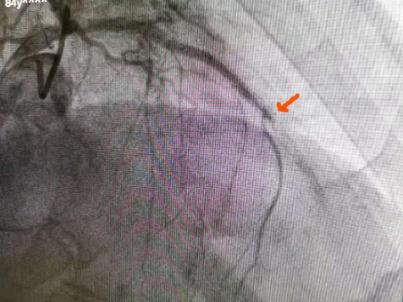

病人許伯,反復(fù)胸悶痛1年,冠脈造影提示為前降支中段重度狹窄,血管分叉處病變,經(jīng)行藥物涂層球囊擴(kuò)張?zhí)幚砗?,癥狀明顯改善。

術(shù)前箭頭所指

術(shù)后箭頭所指